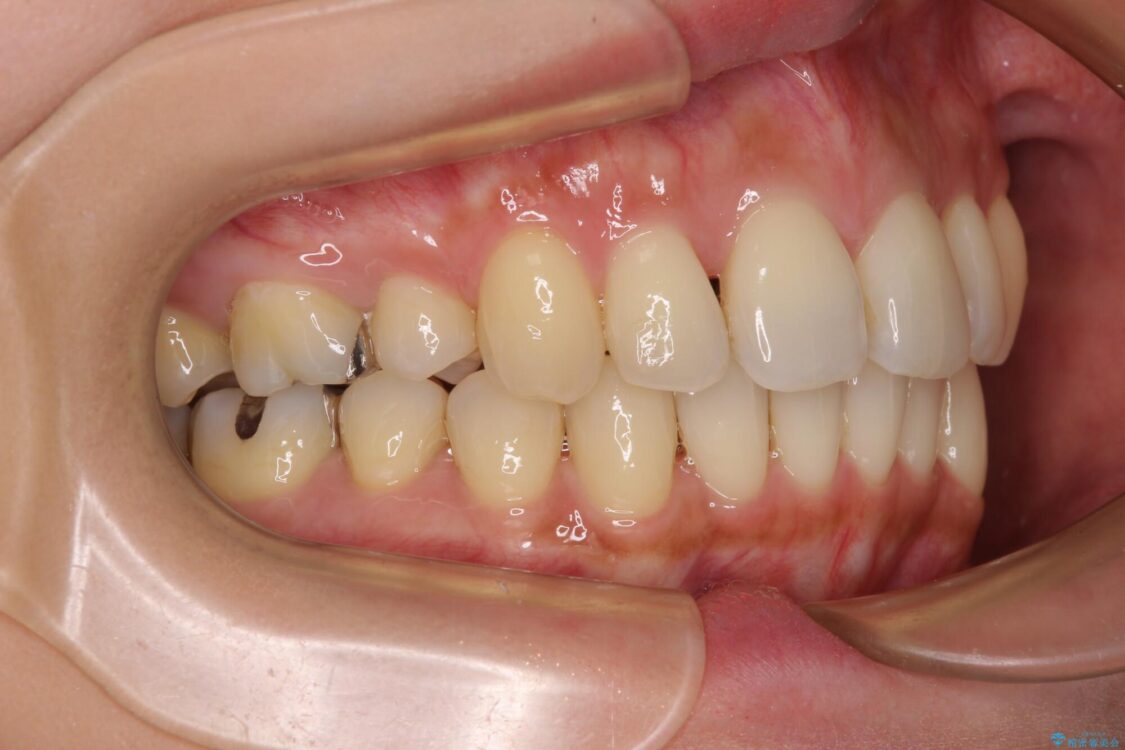

上の前歯の突出感を気にして来院された患者様です。

目立たない装置を希望とのことで、上顎左右第一小臼歯を抜歯し、インビザラインにて矯正治療を行うこととしました。

治療前

• 上顎前歯の突出を軽減 インビザラインによる抜歯矯正 治療前画像